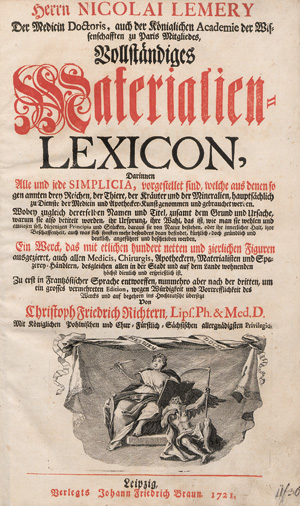

Ebermaier, Johann Erdwin Christoph

Taschenbuch der Chirurgie

Nachverkaufspreis

100€ (US$ 114)